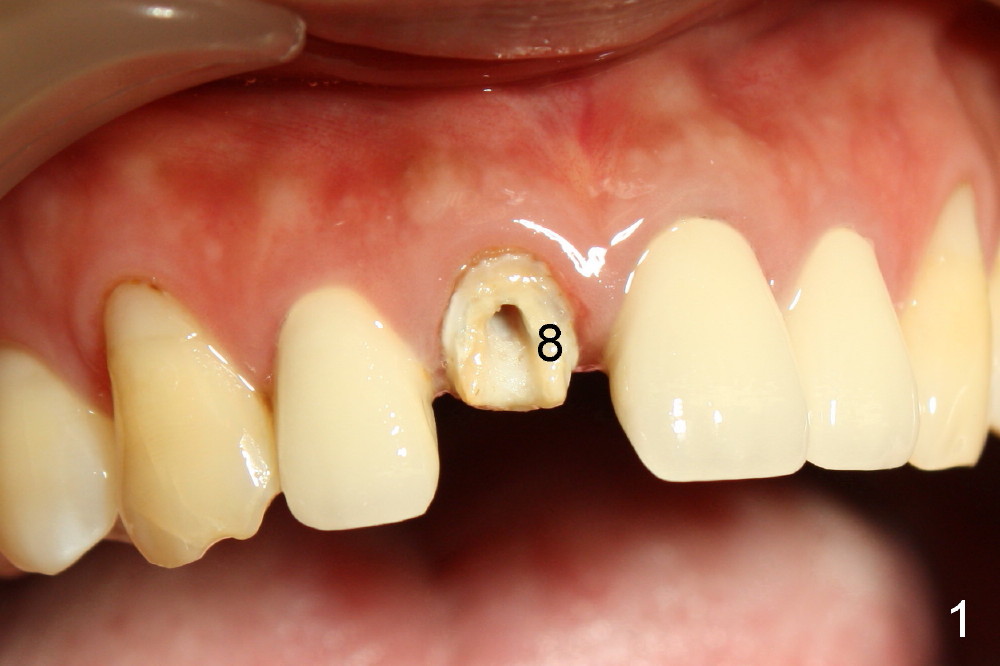

The patient felt better after I & D.  She did not return for irrigation until ten days later (for Christmas).  I & D incision heals.  Swelling and granulation tissue re-appear (Fig.5,6).  In two visits, the implant is stable.